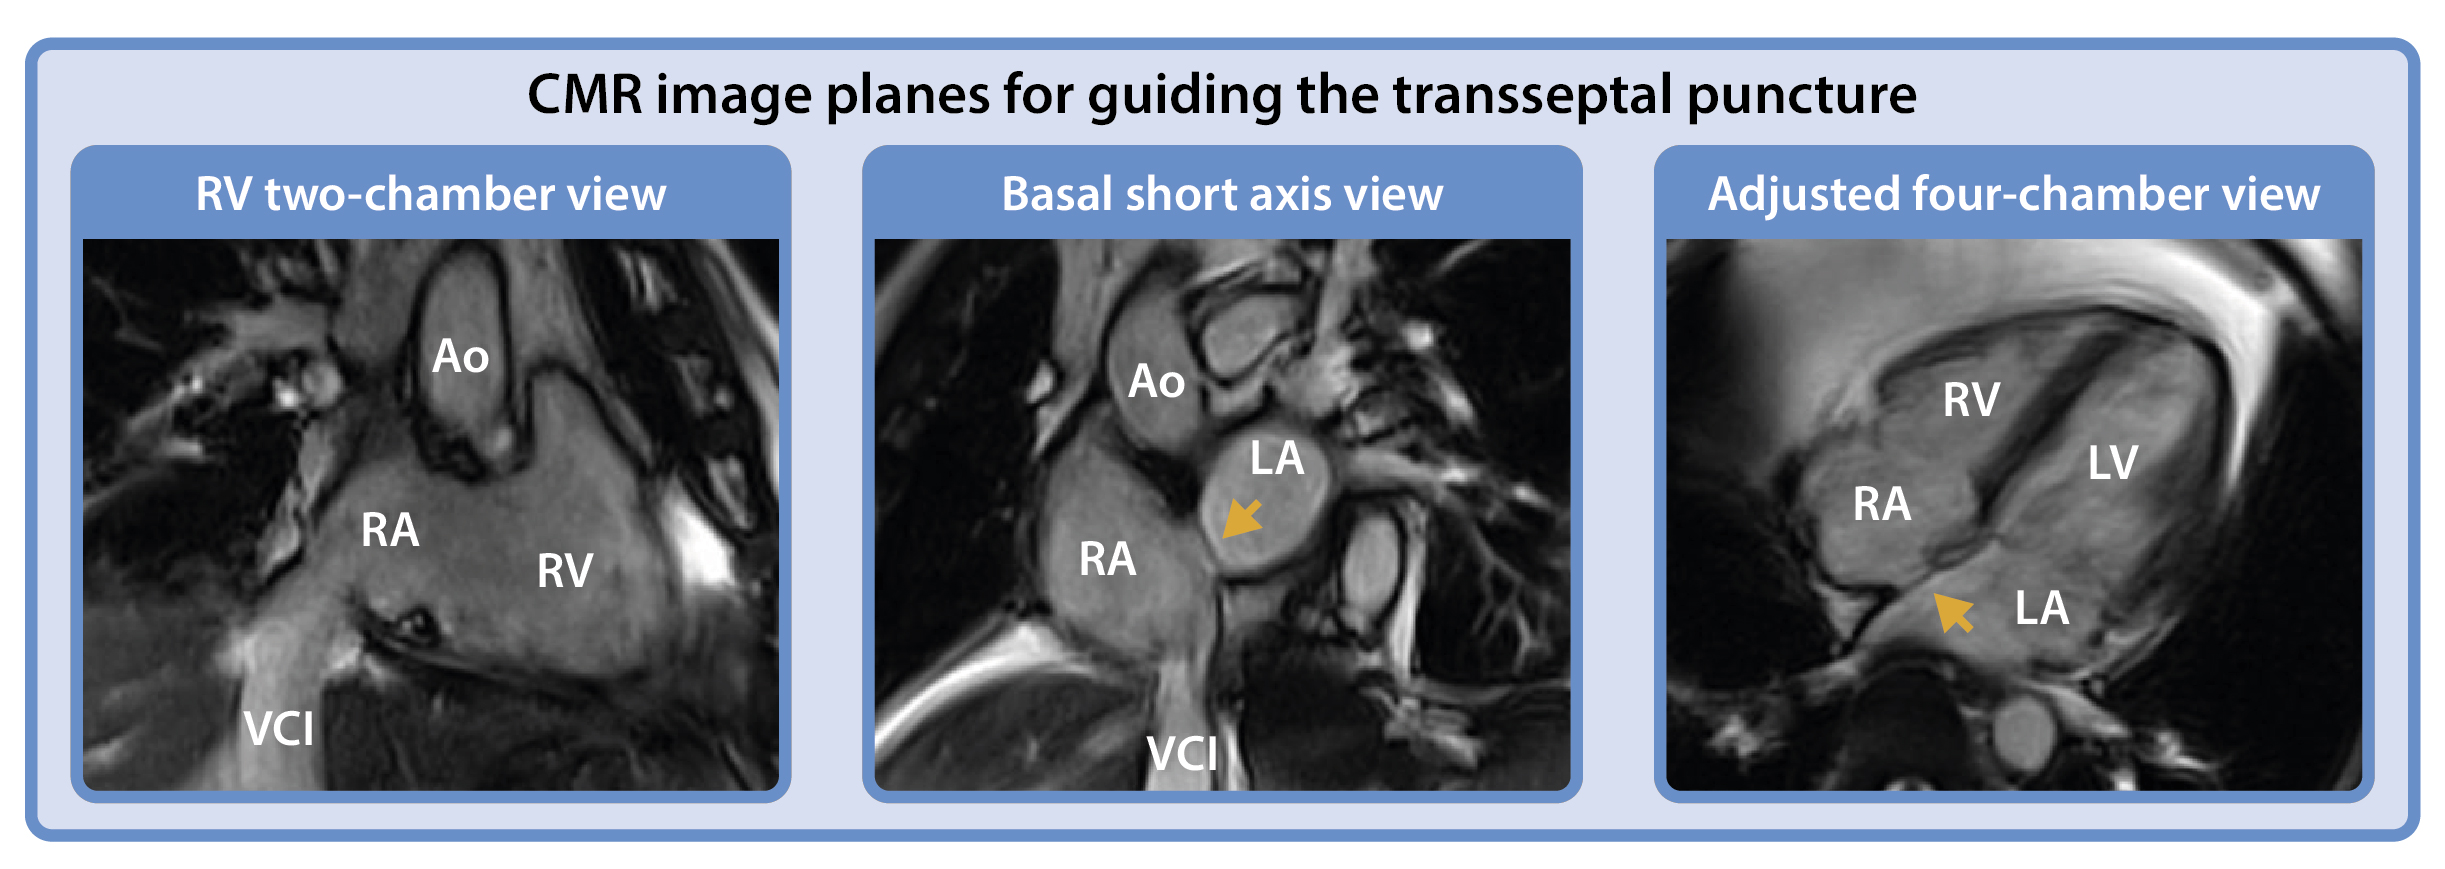

Methods: Real-time MR-guided TSP was performed in a porcine model using an investigational MR-compatible TSP set (Imricor Medical Systems, USA) consisting of a non-ferromagnetic sheath, dilator, and needle. Venous access was obtained via the femoral vein, and devices were advanced through the inferior vena cava into the right atrium. Real-time balanced SSFP imaging in three key planes: adjusted right ventricular (RV) two-chamber, basal short-axis, and four-chamber views, was used to guide catheter positioning and septal engagement. A high-resolution 3D dataset was acquired to generate a segmented anatomical shell of the heart, which was imported into the NorthStar 3D navigation system. Active tracking of the dilator was achieved via integrated miniature receiver coils, enabling continuous localization within the 3D roadmap.

Results: Transseptal access to the left atrium was successfully achieved under real-time MRI guidance. Dedicated imaging planes allowed clear visualization of device movement, septal tenting, and avoidance of critical adjacent structures such as the aortic root and posterior atrial wall. The NorthStar system provided spatial orientation by integrating real-time catheter tracking with the static 3D shell. Following septal puncture, an MR-compatible ablation catheter was advanced into the left atrium and local activation times were recorded to generate a left atrial activation map. Despite passive guidewire limitations, the integrated imaging and navigation approach enabled safe and controlled execution of the TSP.

.jpg) Right ventricular two-chamber view (comparable fluoroscopy orientation: right anterior oblique), basal short axis view (comparable fluoroscopy orientation: left anterior oblique), and four-chamber view. The yellow arrow indicates the foramen ovale.

Right ventricular two-chamber view (comparable fluoroscopy orientation: right anterior oblique), basal short axis view (comparable fluoroscopy orientation: left anterior oblique), and four-chamber view. The yellow arrow indicates the foramen ovale.

Methods: Real-time MR-guided TSP was performed in a porcine model using an investigational MR-compatible TSP set (Imricor Medical Systems, USA) consisting of a non-ferromagnetic sheath, dilator, and needle. Venous access was obtained via the femoral vein, and devices were advanced through the inferior vena cava into the right atrium. Real-time balanced SSFP imaging in three key planes: adjusted right ventricular (RV) two-chamber, basal short-axis, and four-chamber views, was used to guide catheter positioning and septal engagement. A high-resolution 3D dataset was acquired to generate a segmented anatomical shell of the heart, which was imported into the NorthStar 3D navigation system. Active tracking of the dilator was achieved via integrated miniature receiver coils, enabling continuous localization within the 3D roadmap.

Results: Transseptal access to the left atrium was successfully achieved under real-time MRI guidance. Dedicated imaging planes allowed clear visualization of device movement, septal tenting, and avoidance of critical adjacent structures such as the aortic root and posterior atrial wall. The NorthStar system provided spatial orientation by integrating real-time catheter tracking with the static 3D shell. Following septal puncture, an MR-compatible ablation catheter was advanced into the left atrium and local activation times were recorded to generate a left atrial activation map. Despite passive guidewire limitations, the integrated imaging and navigation approach enabled safe and controlled execution of the TSP.

.jpg) Right ventricular two-chamber view (comparable fluoroscopy orientation: right anterior oblique), basal short axis view (comparable fluoroscopy orientation: left anterior oblique), and four-chamber view. The yellow arrow indicates the foramen ovale.

Right ventricular two-chamber view (comparable fluoroscopy orientation: right anterior oblique), basal short axis view (comparable fluoroscopy orientation: left anterior oblique), and four-chamber view. The yellow arrow indicates the foramen ovale. A. Navigation of the MR-compatible TSP set within a 3D static anatomical shell imported into the NorthStar Mapping System, supplemented with adjustable 2D image planes to provide additional spatial orientation and visualization of cardiac motion. B–C. The TSP set was navigated to the foramen ovale (highlighted in red segmentation), with positioning verified across multiple image planes to ensure accurate alignment for septal puncture. The dilator tip is projected onto the shell (yellow arrow). D. Positioning of the dilator tip confirmed on a real-time 4-chamber cine image using active catheter imaging, where the tip appears as a bright signal focus (yellow arrow). E. Following TSP and advancement of the ablation catheter into the left atrium, a 4-chamber cine image confirmed its position, visualized by the catheter tip artifact (yellow arrow) in the left atrium. F. The ablation catheter (yellow arrow) projected in the NorthStar Mapping System during activation mapping of the left atrium.